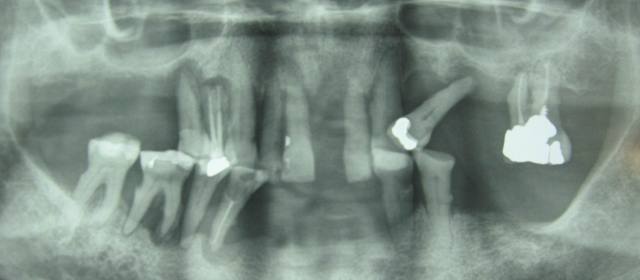

voici un jeune patient vu en urgence, le radiologue du coin fait la pano ds l'urgence aussi

antibio avant de preparer les alvulsions.....

jamais revenu

le france est un pays developpé ou il a tjrs vecu (vive le fluor!!)

même le traitement radiculaire sur 16 est abimé pffff!